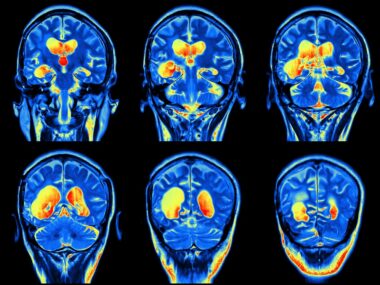

Before I received my relapsing-remitting multiple sclerosis (MS) diagnosis in 2016, I underwent a standard MRI exam, with and without contrast, that scanned my brain, thorax, and cervical spine. I’d never had an MRI before this one. I was vaguely familiar with what the machine looked like, but it’s safe to say that I didn’t know what to expect.

Since being diagnosed, I’ve had to get one to two MRIs each year, and over time, I’ve become used to them, even somewhat numb during them. I think that’s because, regardless of whether I want to undergo an MRI, I have to do it; there’s simply no way around it if I’m to monitor my brain lesions. Thus, I’ve realized and accepted that I’ll have to get MRIs for the rest of my life. Or at least, I thought I’d accepted this reality.